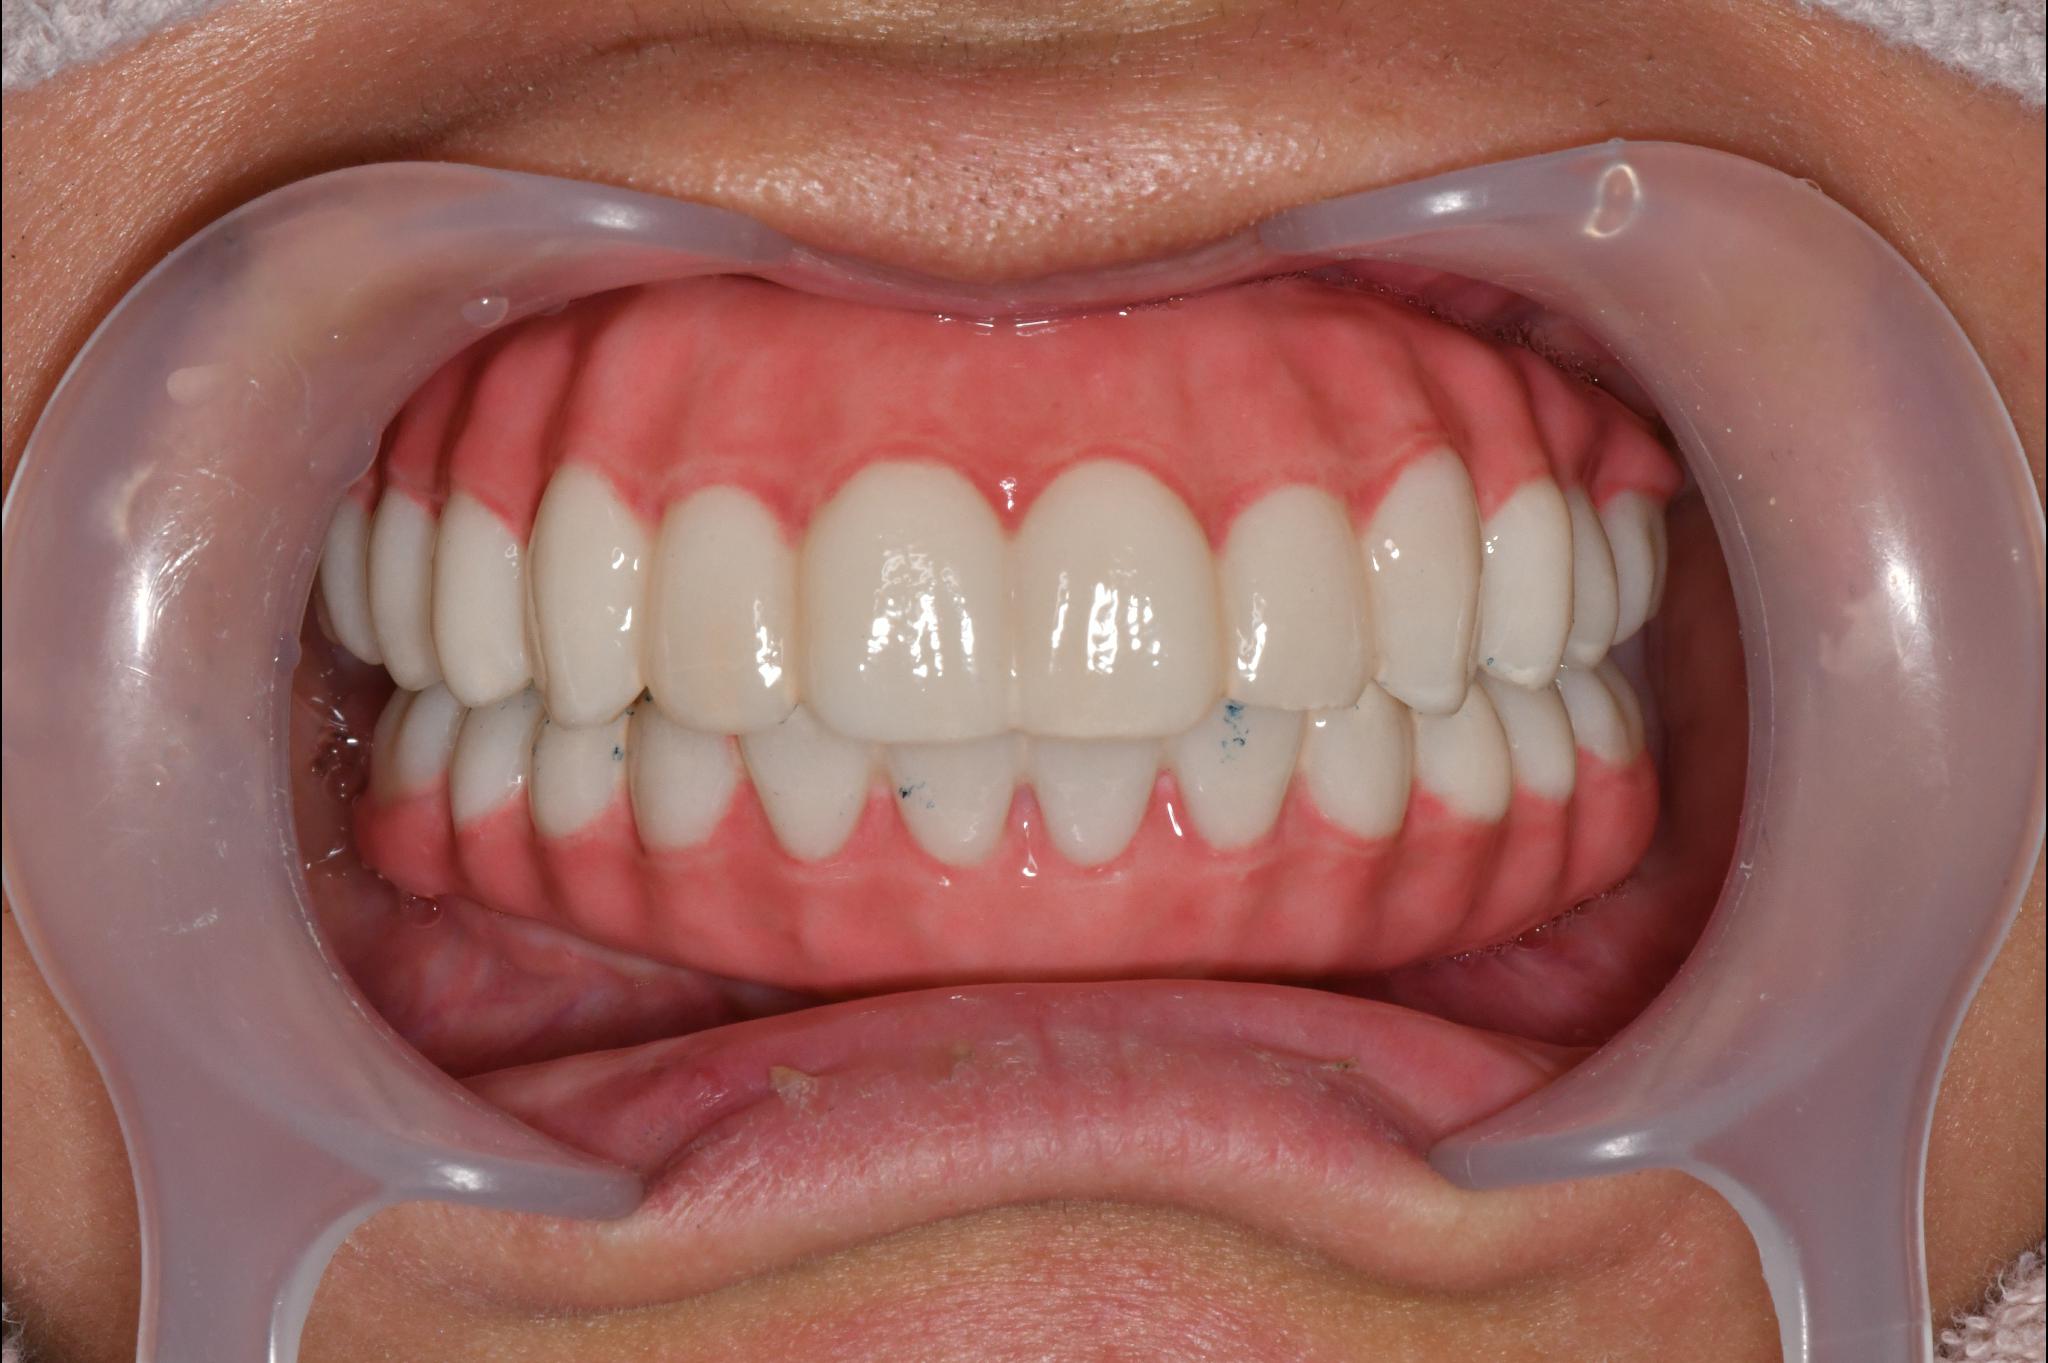

福岡県 49歳(男性)

「長年の口元の不安が負担」

術前

術後

内容 :上下顎オールオン4ザイゴマ0

費用 :4,989,600円

※モニター価格

期間 :半年

リスク:出血・腫れ・痺れ・痛み

他院でインプラント治療を行っていましたが突然閉院となり、治療が中断されてしまいました。噛み合わせや歯並びに深刻な悩みを抱えることになり、口元の不安が負担になっていました。

相談の中でわずか1日で固定式の歯が入るスピード感に大きな魅力を感じました。

「ここなら長年の悩みが無くなるかもしれない」と感じ、手術を受ける決断をしました。

手術当日に歯が入り、その即時性に深く満足しています。これまでは人前で笑えないことが最大の悩みでしたが、これからは笑顔が増えていきそうです。